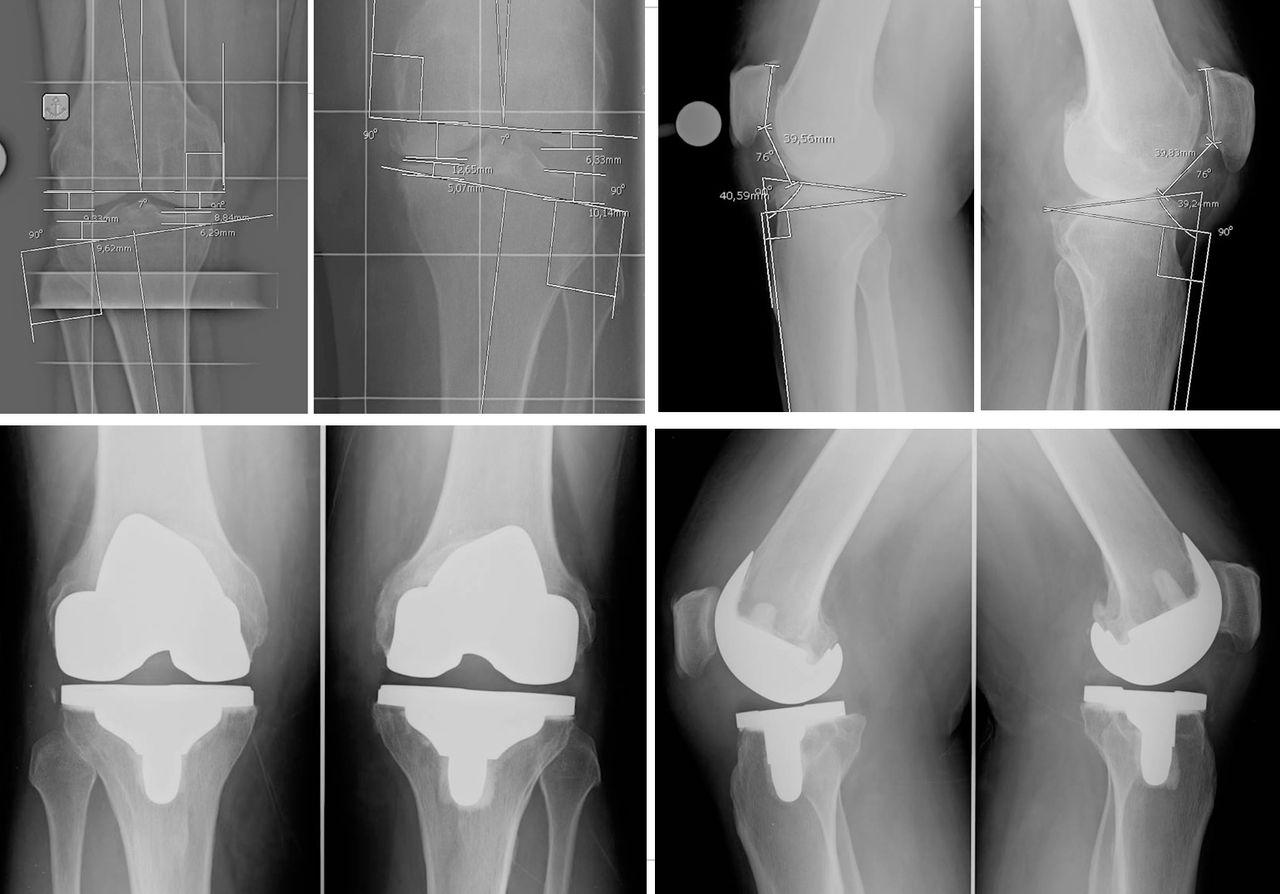

Il Dr. Giuntoli si è laureato in Medicina e Chirurgia nel 2014 presso l’Università degli Studi di Firenze e successivamente nel 2020, ha conseguito la Specializzazione in Ortopedia e Traumatologia presso l’Università degli Studi di Pisa con votazione di 110/110 e Lode, discutendo la tesi: “I sensori di pressione nella Protesi Totale di Ginocchio: confronto clinico e funzionale mediante Gait Analysis tra la tecnica convenzionale e il sistema VERASENSE”. Dal 2021 al 2024 ha svolto attività clinica, chirurgica ed universitaria presso la U.O. Ortopedia e Traumatologia I Universitaria dell'Azienda Ospedaliero Universitaria Pisana (AOUP) nell'Ospedale di Cisanello di Pisa Da gennaio 2023 svolge attività di docenza di ecografia muscoloscheletrica diagnostica e procedurale (infiltrativa) presso la scuola SIUMB di Pisa, di cui è anche docente dal 2024 presso l'Università di Pisa. Attualmente Dirigente Medico presso il CESAT (Centro Eccellenza Sostituzione Articolare Regione Toscana) - Ospedale San Pietro Igneo di Fucecchio, presso la quale svolge la maggior parte dell'attività clinica, chirurgica e di ricerca soprattutto nell'ambito della protesica di anca e ginocchio e dell'artroscopia di ginocchio. Da settembre 2023 svolge attività chirurgica anche presso la casa di cura privata San Rossore di Pisa e la casi di cura privata San Paolo di Pistoia. Istruzione e Formazione: • Laurea in Medicina e Chirurgia presso Università degli Studi di Firenze in data 28/10/14 • Specializzazione in Ortopedia e Traumatologia presso Università degli Studi di Pisa in data 17/11/20 • Il Dott. Michele Giuntoli ha partecipato a numerosi corsi di aggiornamento e perfezionamento in Italia e all'estero e collabora, attualmente, con le principali società scientifiche ortopediche nazionali ed internazionali • In qualità di relatore ha preso parte a diversi congressi e seminari ed è autore di diverse pubblicazioni scientifiche pubblicate su riviste del settore nazionali ed internazionali Dal 2015 al 2020 ha svolto attività di formazione c/o la Scuola di Specializzazione in Ortopedia e Traumatologia dell’Università degli Studi di Pisa (sotto la direzione del Prof. Lisanti e del Prof. Capanna effettuando attività clinica e chirurgica di Ortopedia e Traumatologia maggiore e minore in qualità di Specializzando presso le U.O. di Ortopedia e Traumatologia I (Dir. Prof. Scaglione) e II (Dir. Prof. Capanna) della medesima Università. Nel 2019 e nel 2020 ha frequentato in qualità di Specializzando la U.O. di Ortopedia e Traumatologia dell'Ospedale F. Lotti di Pontedera (Dir. F. Carnesecchi), dell'Ospedale Versilia di Lido di Camaiore (Dir. M. Manca) ed anche presso l'Ospedale di Livorno (Dir. A. Augusti), svolgendo prevalentemente attività chirurgica di Ortopedia e Traumatologia maggiore e minore. Nel 2018, in qualità di specializzando, ha effettuato una fellowship internazionale presso il Dipartimento di Chirurgia Ortopedica e Bio-ingegneria della Scuola di Medicina della Stanford University (Palo Alto, California, USA) svolgendo gran parte dell'attività di ricerca sulla chirurgia protesica di ginocchio al VA Health Care System di Palo Alto sotto la supervisione del Prof. Pier Francesco Indelli. Ha acquisito nell'anno 2021 competenze ecografiche per l'apparato muscolo-scheletrico ottenendo il diploma nazionale SIUMB. Premi e riconoscimenti: •Vincitore Borsa di Studio OTODI Young Conseguita presso il 50° Congresso Nazionale OTODI (Sorrento, 23-24 Maggio 2019) in data 24 maggio 2019 con la presentazione Elettronica “Protesi totale di ginocchio primaria total stabilizer: risultati clinici e strumentali a breve-medio termine” Pubblicazioni • https://www.researchgate.net/profile/Michele_Giuntoli • https://scholar.google.com/citations?hl=it&user=TY6iufsAAAAJ • https://pubmed.ncbi.nlm.nih.gov/?term=giuntoli%2C+michele%5BAuthor%5D&sort= Enti e società scientifiche: - SIOT (Società Italiana di Ortopedia e Traumatologia) - OTODI (Ortopedici Traumatologi Ospedalieri d'Italia) - ESSKA (European Society of Sports Traumatology, Knee Surgery and Arthroscopy) - EKA (European Knee Associates) - SIUMB (Società Italiana in Ultrasonologia in Medicina e Biologia). Abilitazione: • Ordini dei Medici Chirurghi e degli Odontoiatri (FNOMCEO) n. 2233 iscritto il 19/02/2015

• Chirurgia del ginocchio

• Chirurgia protesica con robot

• Protesi ginocchio